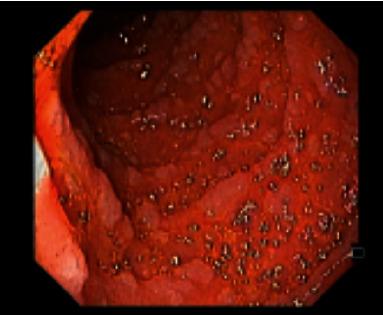

Gardner's syndrome is an autosomal dominant disease caused by a mutation in the gene with 20-30% of cases presenting de novo. This entity is a variant of familial adenomatous polyposis, with a prevalence of 3/100,000 habitants. It may present as early as 2 months of age with a variety of both colonic and extracolonic symptoms. We report a case of a 21-year-old man, without any known family history, presenting with microcytic hypochromic anemia and constitutional symptoms for two months. Ultimately, after the etiological study, Gardner syndrome diagnosis was established as an index primary familiar case. Gardner syndrome is a clinical challenge which requires a prompt suspicion in order to reach its diagnosis. Given the malignant evolution of adenomas in 100% of untreated patients, early identification of extraintestinal manifestations (identifiable prior to colonic symptoms) is of the essence. A consequent endoscopic study to confirm gastrointestinal involvement is essential for a more favorable prognosis.

加德纳综合征是一种常染色体显性疾病,由该基因的突变引起,20%至30%的病例为新发。该病症是家族性腺瘤性息肉病的一种变体,发病率为十万分之三。它最早可在2个月大时出现,伴有多种结肠和结肠外症状。我们报告一例21岁男性病例,无任何已知家族病史,出现小细胞低色素性贫血和全身症状达两个月。最终,经过病因学研究,加德纳综合征被诊断为原发性家族性病例。加德纳综合征是一项临床挑战,需要迅速怀疑以便做出诊断。鉴于100%未经治疗的患者腺瘤会发生恶性演变,早期识别肠外表现(在结肠症状出现之前即可识别)至关重要。因此,进行内镜检查以确认胃肠道受累对于获得更良好的预后至关重要。